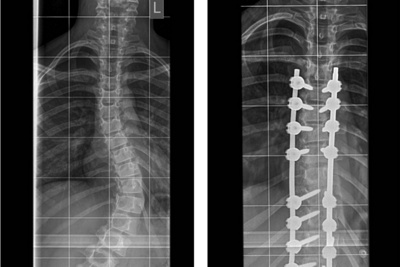

However, in Dané’s case the brace failed to correct the curve sufficiently. The specialist then recommended surgery, which involves inserting rods and screws around the spine to straighten it.

In the years following her diagnosis, Dané did not get consistent X-rays and the COVID-19 pandemic further delayed investigations. But when Nicolene saw how pronounced her curve had become, she made an appointment with Dr Pillay, who discovered that it had progressed to 56°. Dané subsequently wore a fitted brace for around a year. At the beginning of 2023, despite initial progress, Dr Pillay found her back had again begun deteriorating and he recommended surgery. The surgery went ahead on 30 October, allowing Dané time to complete her growth spurt.

“We cut through the back and do an open surgery, putting screws on either side of the spine. Then we bend the rod according to the normal curvature of the spine, manipulating the spine back into its straight position. We also make carefully planned cuts that assist in making the spine straighter.” Patients stay in hospital for about 3-4 days and the recovery period is around six weeks, with the final follow-up appointment three months post-surgery. Patients are then sent to a biokineticist for exercises to prevent future problems.